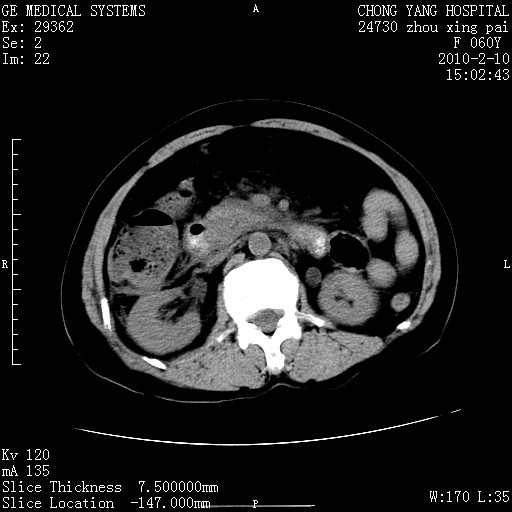

标题: CT24682:F60Y 腹痛 其它不详 [打印本页]

标题: CT24682:F60Y 腹痛 其它不详

1)胆总管末端梗阻,不排除结石所致可能。2)胰腺炎。3)慢性胆囊炎可能。4)左侧输尿管上段扩张。5)少量腹水。6)双侧少量胸腔积液,伴两下肺部分肺萎陷。

1)胆囊炎。2)胆源性胰腺炎。3)右肾周筋膜增厚,肾旁前间隙积液。4)左侧输尿管上段扩张。5)少量腹水。6)双侧少量胸腔积液,伴两下肺部分肺膨胀不全。

1)胆总管末端梗阻。2)胰腺炎。3)慢性胆囊炎可能。4)左侧输尿管上段扩张。5)少量腹水。6)双侧少量胸腔积液,伴两下肺部分肺萎陷。